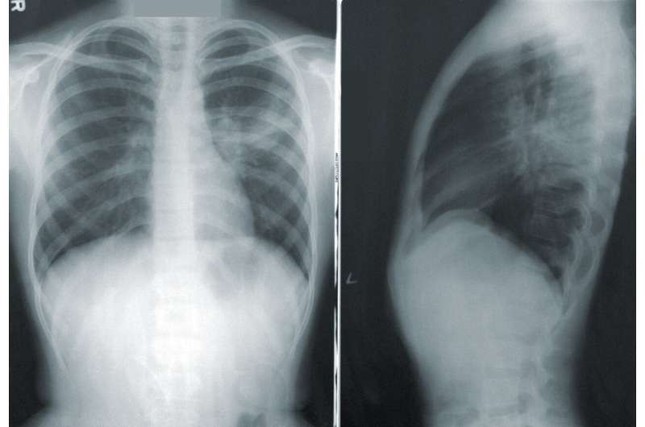

16/06/2024 23:20Tìm ra nguyên nhân vì sao nhiều người không bao giờ hút thuốc lá lại bị ung thư phổi

Nghiên cứu được công bố trên tạp chí Nature Communications cho thấy các tế bào ung thư phổi với hai đột biến gien đặc biệt có nhiều khả năng nhân đôi bộ gien của chúng, giúp chúng chịu đựng được và phát triển khả năng kháng lại.

Ở Anh, ung thư phổi là loại ung thư phổ biến thứ ba và là nguyên nhân hàng đầu gây tử vong do ung thư. Khoảng 85% bệnh nhân ung thư phổi (NSCLC) phổ biến nhất được tìm thấy ở những bệnh nhân chưa bao giờ hút thuốc. Do đó, ung thư phổi "không bao giờ hút thuốc" là nguyên nhân gây tử vong do ung thư phổ biến thứ năm trên thế giới.

Chưa bao giờ hút thuốc lá , cũng mắc ung thư phổi

Đột biến gien phổ biến nhất được tìm thấy trong NSCLC là ở gien thụ thể tăng trưởng biểu bì (EGFR), cho phép các tế bào ung thư phát triển nhanh hơn. Nó được tìm thấy trong khoảng 10–15% trường hợp NSCLC ở Anh, đặc biệt ở những bệnh nhân chưa bao giờ hút thuốc.

Tỷ lệ sống sót khác nhau tùy thuộc vào mức độ tiến triển của bệnh ung thư, chỉ có khoảng một phần ba số bệnh nhân mắc NSCLC Giai đoạn IV và đột biến EGFR sống sót được tới ba năm.

Các phương pháp điều trị ung thư phổi nhắm vào đột biến này, được gọi là chất ức chế EGFR, đã có từ hơn 15 năm nay. Tuy nhiên, trong khi một số bệnh nhân nhận thấy khối u ung thư của họ co lại khi sử dụng thuốc ức chế EGFR thì những bệnh nhân khác, đặc biệt là những người có đột biến bổ sung ở gen p53 (có vai trò ức chế khối u ), lại không đáp ứng và có tỷ lệ sống sót tồi tệ hơn nhiều . Thế nhưng, các nhà khoa học và bác sĩ lâm sàng cho đến nay vẫn chưa thể giải thích được tại sao lại như vậy.

Để tìm ra câu trả lời, các nhà nghiên cứu đã phân tích lại dữ liệu từ các thử nghiệm về chất ức chế EGFR mới nhất, osimertinib, do AstraZeneca phát triển. Họ đã xem xét các bản quét cơ bản và các lần quét tiếp theo đầu tiên được thực hiện sau vài tháng điều trị cho những bệnh nhân chỉ có EGFR hoặc có đột biến EGFR và p53.

Nhóm nghiên cứu đã so sánh từng khối u trên bản quét, nhiều hơn so với những gì được đo trong thử nghiệm ban đầu. Họ phát hiện ra rằng, đối với những bệnh nhân chỉ có đột biến EGFR, tất cả các khối u đều nhỏ hơn để đáp ứng với điều trị. Nhưng đối với những bệnh nhân có cả hai đột biến, trong khi một số khối u đã thu nhỏ lại thì những khối u khác lại phát triển, cung cấp bằng chứng về tình trạng kháng thuốc nhanh chóng. Kiểu phản ứng này, khi một số chứ không phải tất cả các vùng ung thư đều co lại để đáp ứng với việc điều trị bằng thuốc ở từng bệnh nhân, được gọi là "phản ứng hỗn hợp" và là một thách thức đối với các bác sĩ ung thư chăm sóc bệnh nhân ung thư.

Để tìm hiểu lý do tại sao một số khối u ở những bệnh nhân này có thể dễ bị kháng thuốc hơn, nhóm nghiên cứu đã nghiên cứu mô hình chuột có cả đột biến EGFR và p53. Họ phát hiện ra rằng, trong các khối u kháng thuốc ở những con chuột này, nhiều tế bào ung thư đã nhân đôi bộ gien của chúng, mang lại cho chúng thêm bản sao của tất cả các nhiễm sắc thể.

Tiến sĩ Crispin Hiley, từ Viện Ung thư UCL và là Bác sĩ tư vấn ung thư lâm sàng tại UCLH, cho biết: "Một khi chúng tôi có thể xác định được những bệnh nhân có cả đột biến EGFR và p53 có khối u biểu hiện toàn bộ bộ gien tăng gấp đôi, chúng tôi có thể điều trị những bệnh nhân này theo cách chọn lọc hơn. Điều này có thể có nghĩa là theo dõi chuyên sâu hơn, xạ trị sớm hoặc cắt bỏ để nhắm vào các khối u kháng thuốc hoặc sử dụng sớm sự kết hợp các chất ức chế EGFR, như osimertinib, với các loại thuốc khác bao gồm cả hóa trị”.